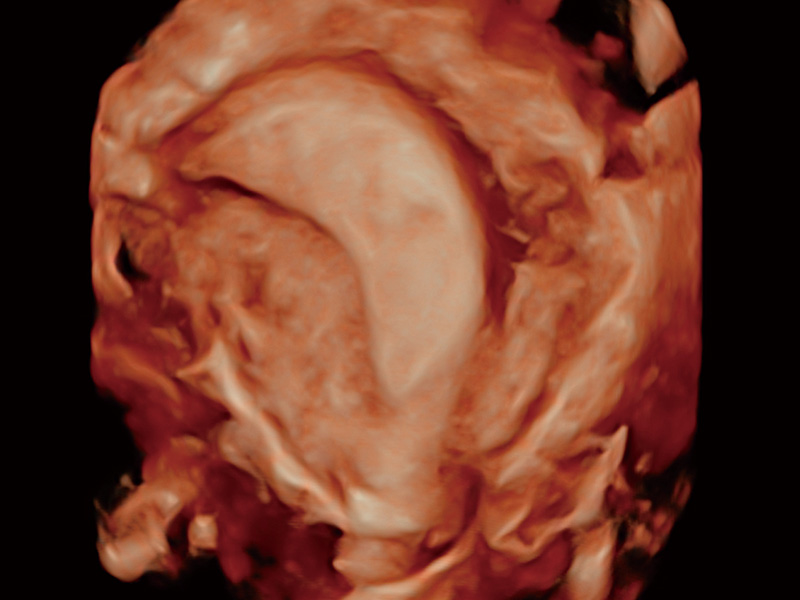

临床图

卵巢多囊样改变